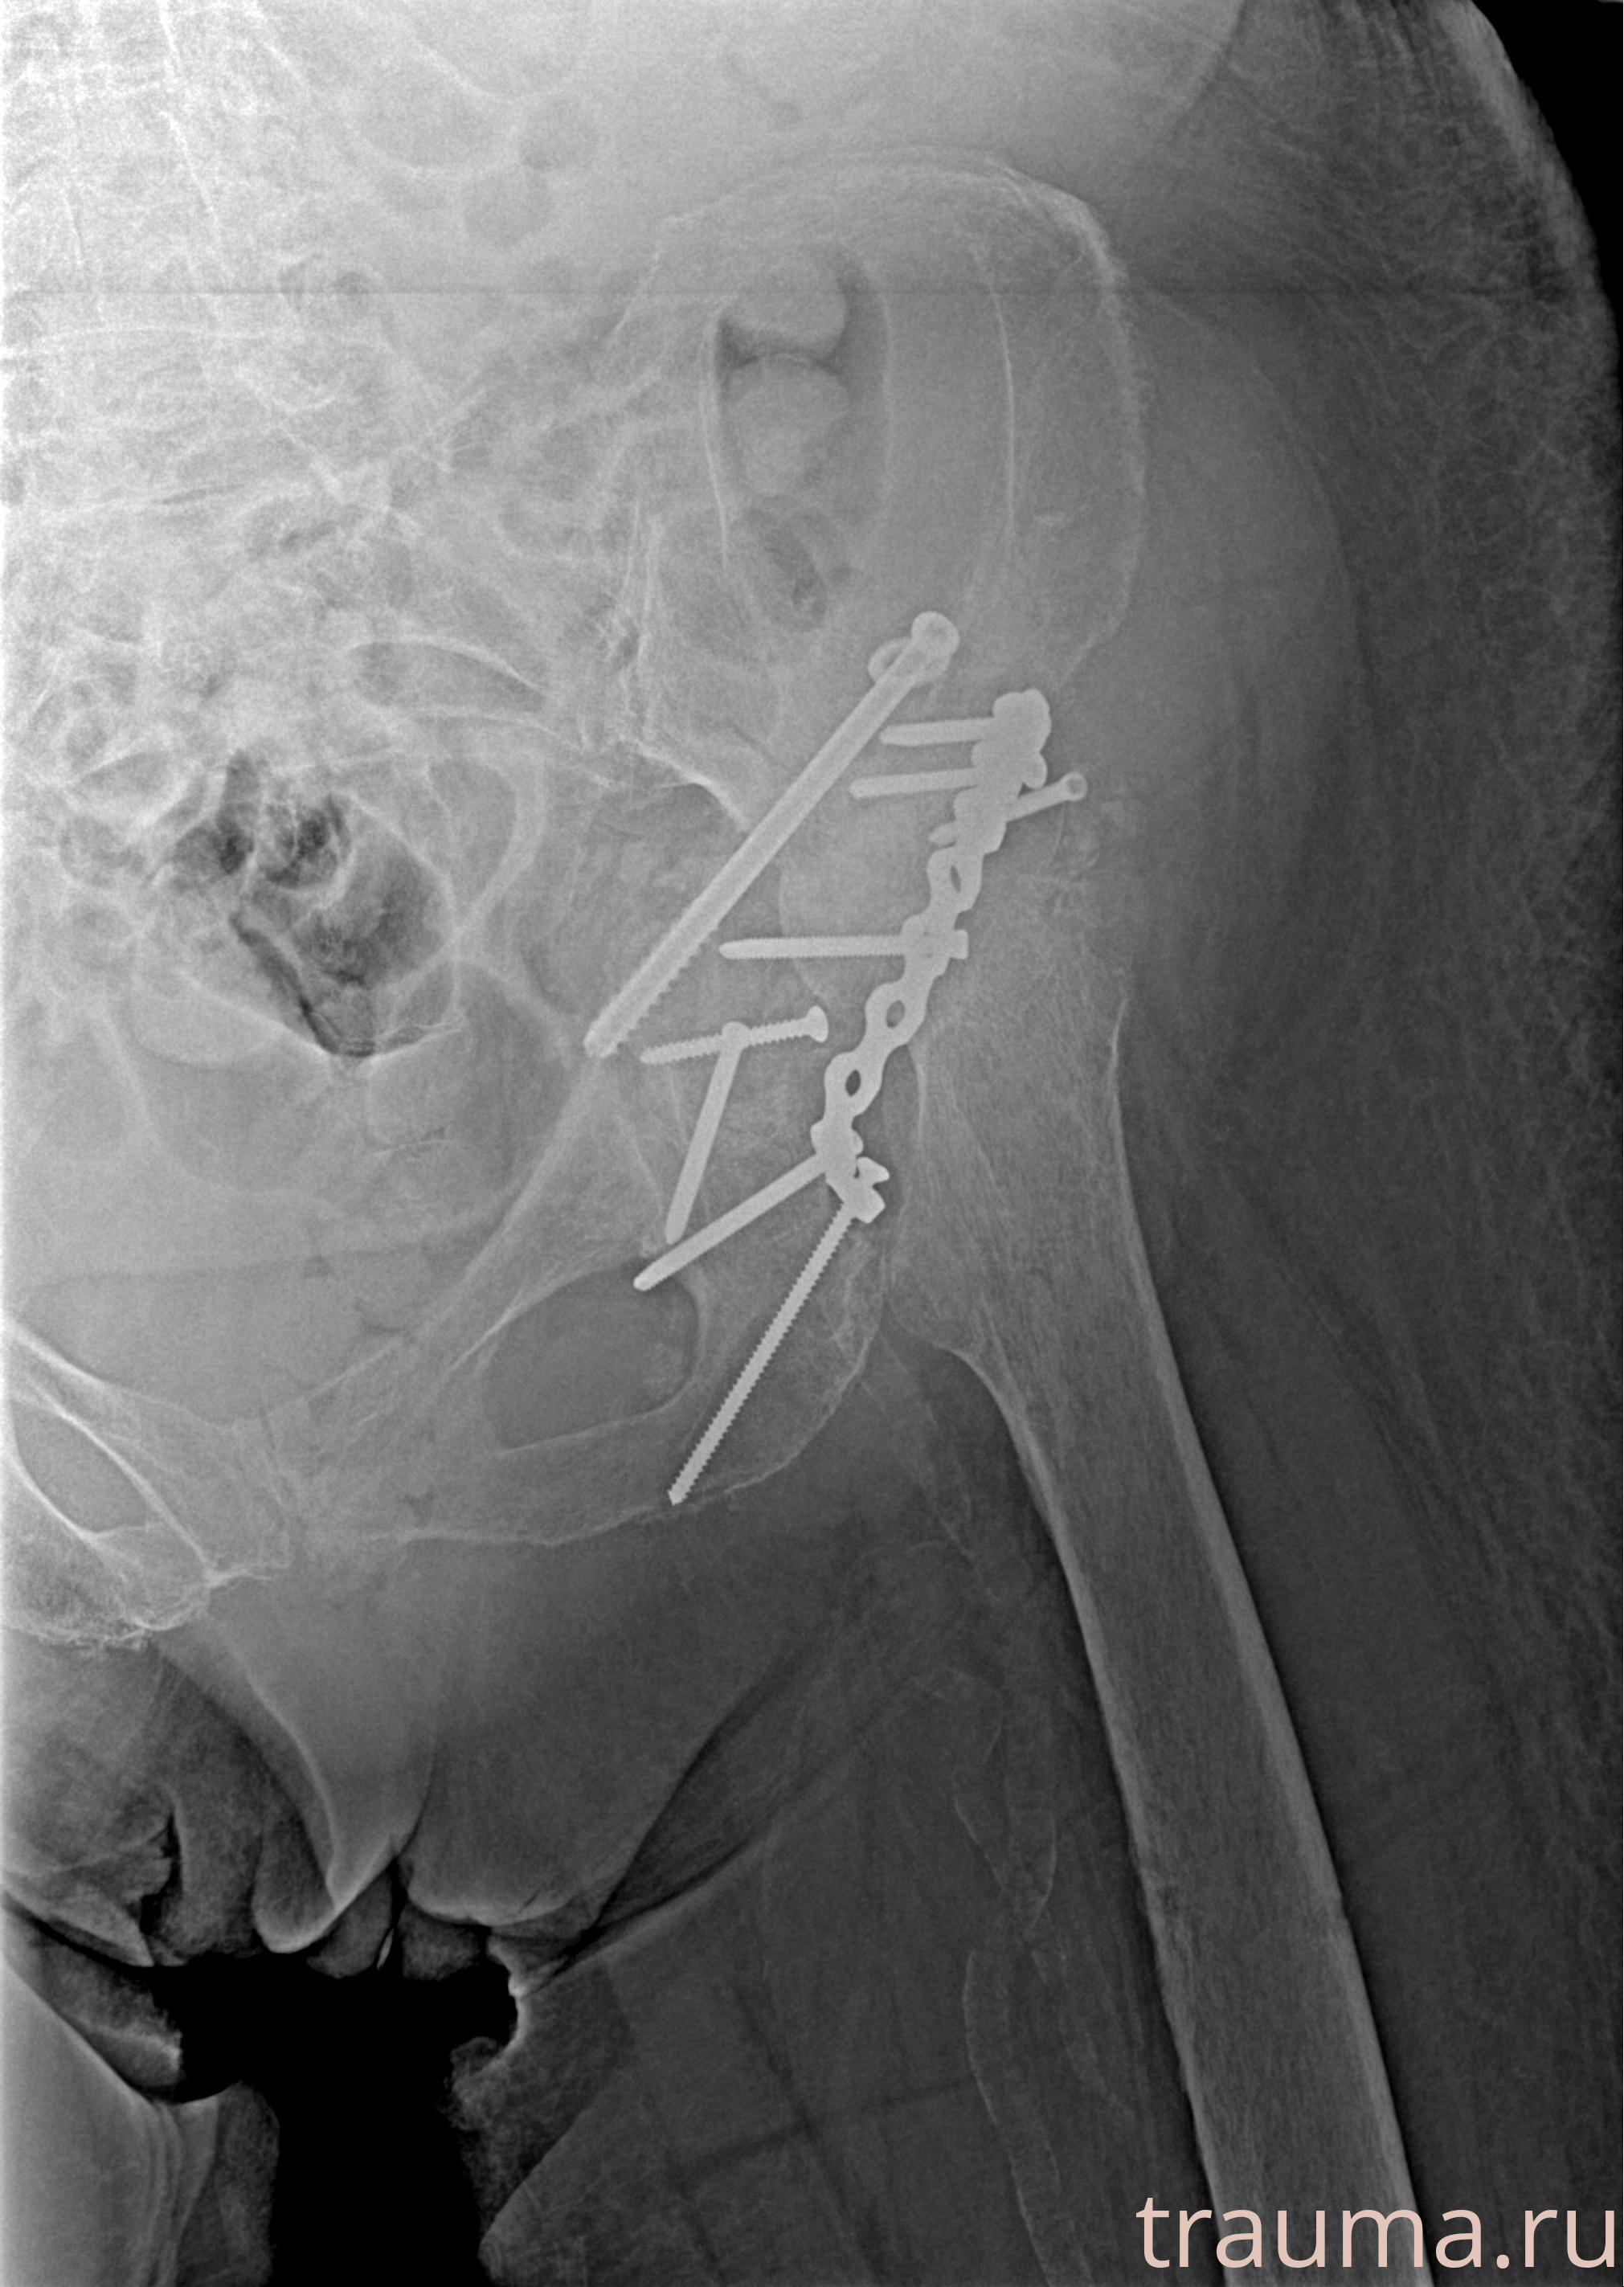

Рентгенограммы